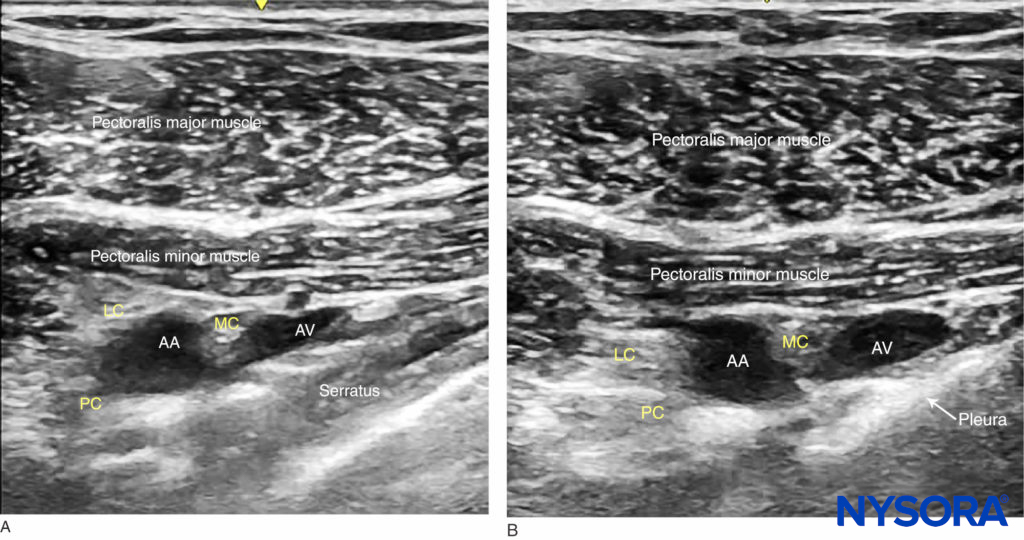

The axillary artery can be identified deep to the pectoralis major and minor muscles. An effort needs to be made to obtain clear views of both pectoralis muscles and their respective fasciae. This is important because the area of interest lies underneath the fascia of the pectoralis minor muscle. Surrounding the artery are the three cords of the brachial plexus: the lateral, posterior, and medial cords. These are named for their usual position relative to the axillary artery, although there is a great deal of anatomical variation. With the left side of the screen corresponding to the cephalad aspect, the cords can often be seen as round hyperechoic structures at the positions of approximately 9 o’clock (lateral cord), 7 o’clock (posterior cord), and 5 o’clock (medial cord) (Figures 2 and 3). The axillary vein is seen as a compressible hypoechoic structure that lies medially to the axillary artery. Multiple other, smaller vessels (eg, the cephalic vein) are often present as well. The transducer is moved in the cephalad-caudad and medial-lateral direction until the artery is identified in cross-section. Depending on the depth selected and the level at which the scanning is performed, the chest wall and the pleura may be seen in the medial and more caudal aspect of the image. The axillary artery and/or brachial plexus are typically identified at a depth of 3–5 cm in average-size patients.

FIGURE 3. Ultrasound image of the brachial plexus (BP) distal to the clavicle. Note that the BP, axillary artery (AA) and axillary vein (AV) are located below the fascia (red line) of the pectoralis minor muscle (PMiM). LC, lateral cord; MC, medial cord; PC, posterior cord; PMaM, pectoralis major muscle.

strong>FIGURE 5. Ultrasound-guided infraclavicular nerve block: a medial-to-lateral probe movement is used to avoid the area where the needle advanced in the parasagittal plane could enter the pleura. (A) Parasagittal lateral view: the serratus anterior is seen between the neurovascular bundle and the pleura. (B) In this probe position, the pleura lies closer to the brachial plexus.